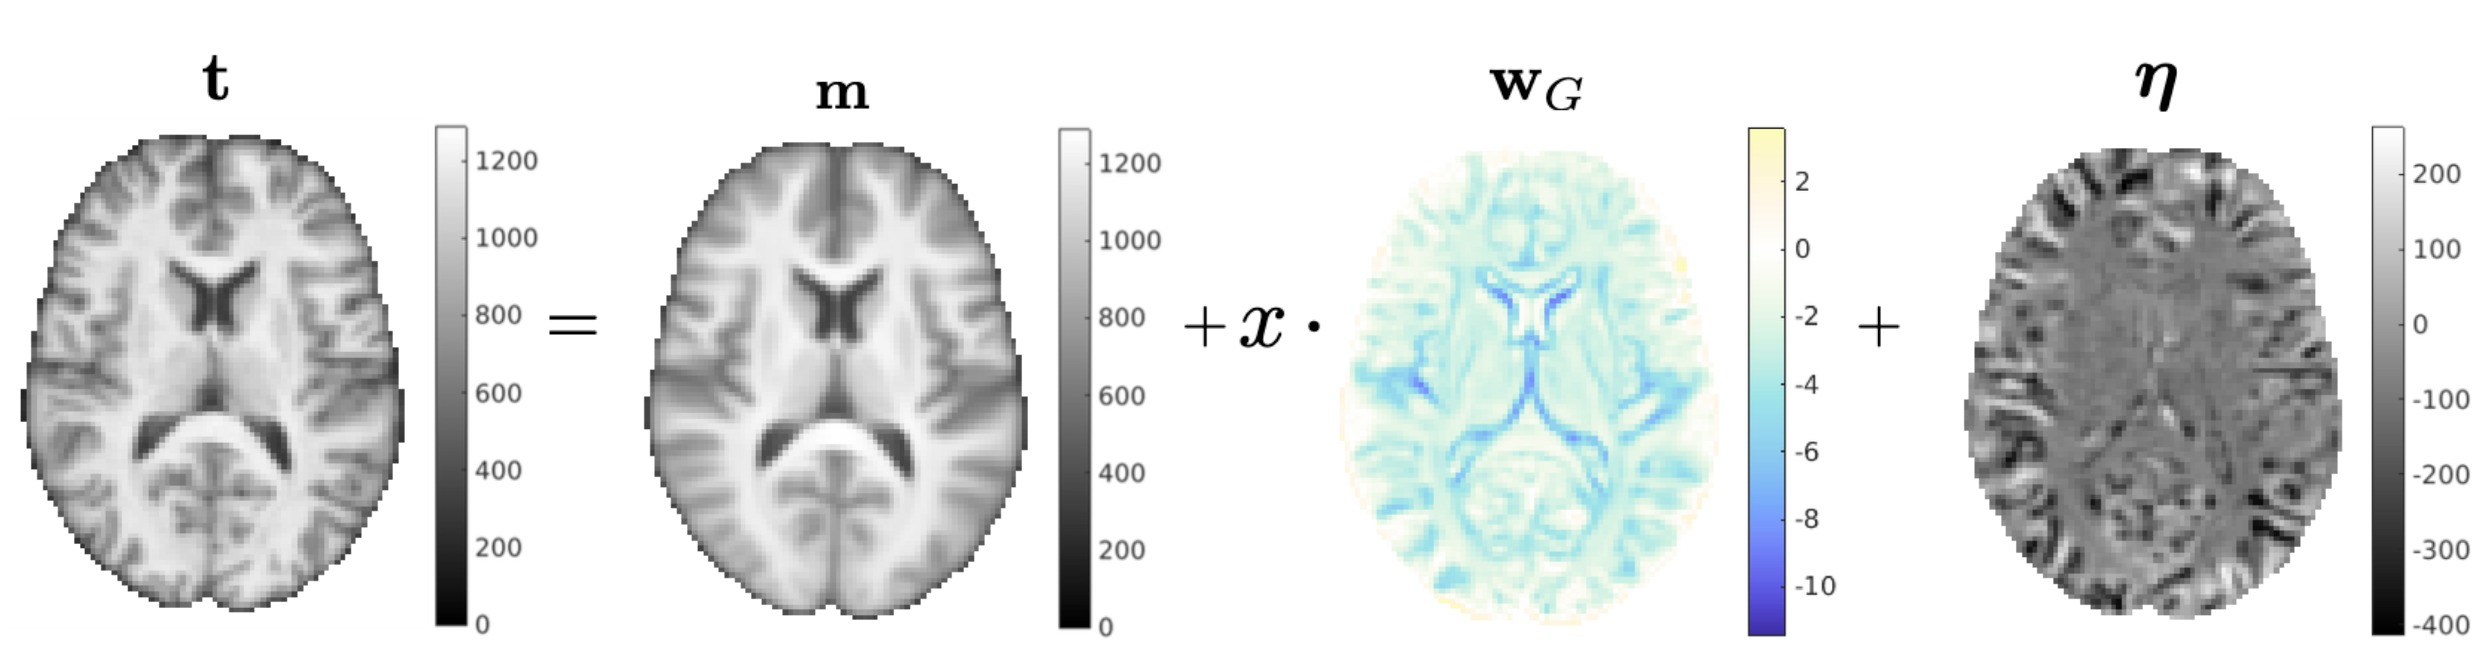

Let denote a a vector that contains the intensities in the voxels of a subject’s image, and a scalar variable of interest about that subject (such as their age or gender). A simple generative model, illustrated in Fig. 1, is then of the form

| (1) |

Here is a spatial weight map – referred to as the generative weight map in the remainder – that reflects how strongly the variable of interest is expressed in the voxels of : Assuming a causal relationship between and , it encodes how a unit increase changes each voxel’s intensity, on average. Further, is a spatial template of intensities at baseline (i.e., when ), and is a random noise vector, assumed to be Gaussian distributed with zero mean and covariance . For notational convenience we will collect the two spatial weight maps and in a single matrix for the remainder of the paper.

where (cf. A). The predicted value of is therefore given by (6), which again involves taking the inner product of the discriminative weights with . An example of model inversion in case of age prediction is shown in Fig. 2.